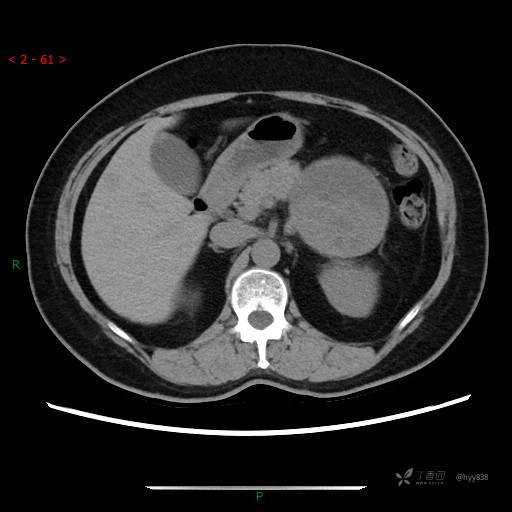

增强动脉期